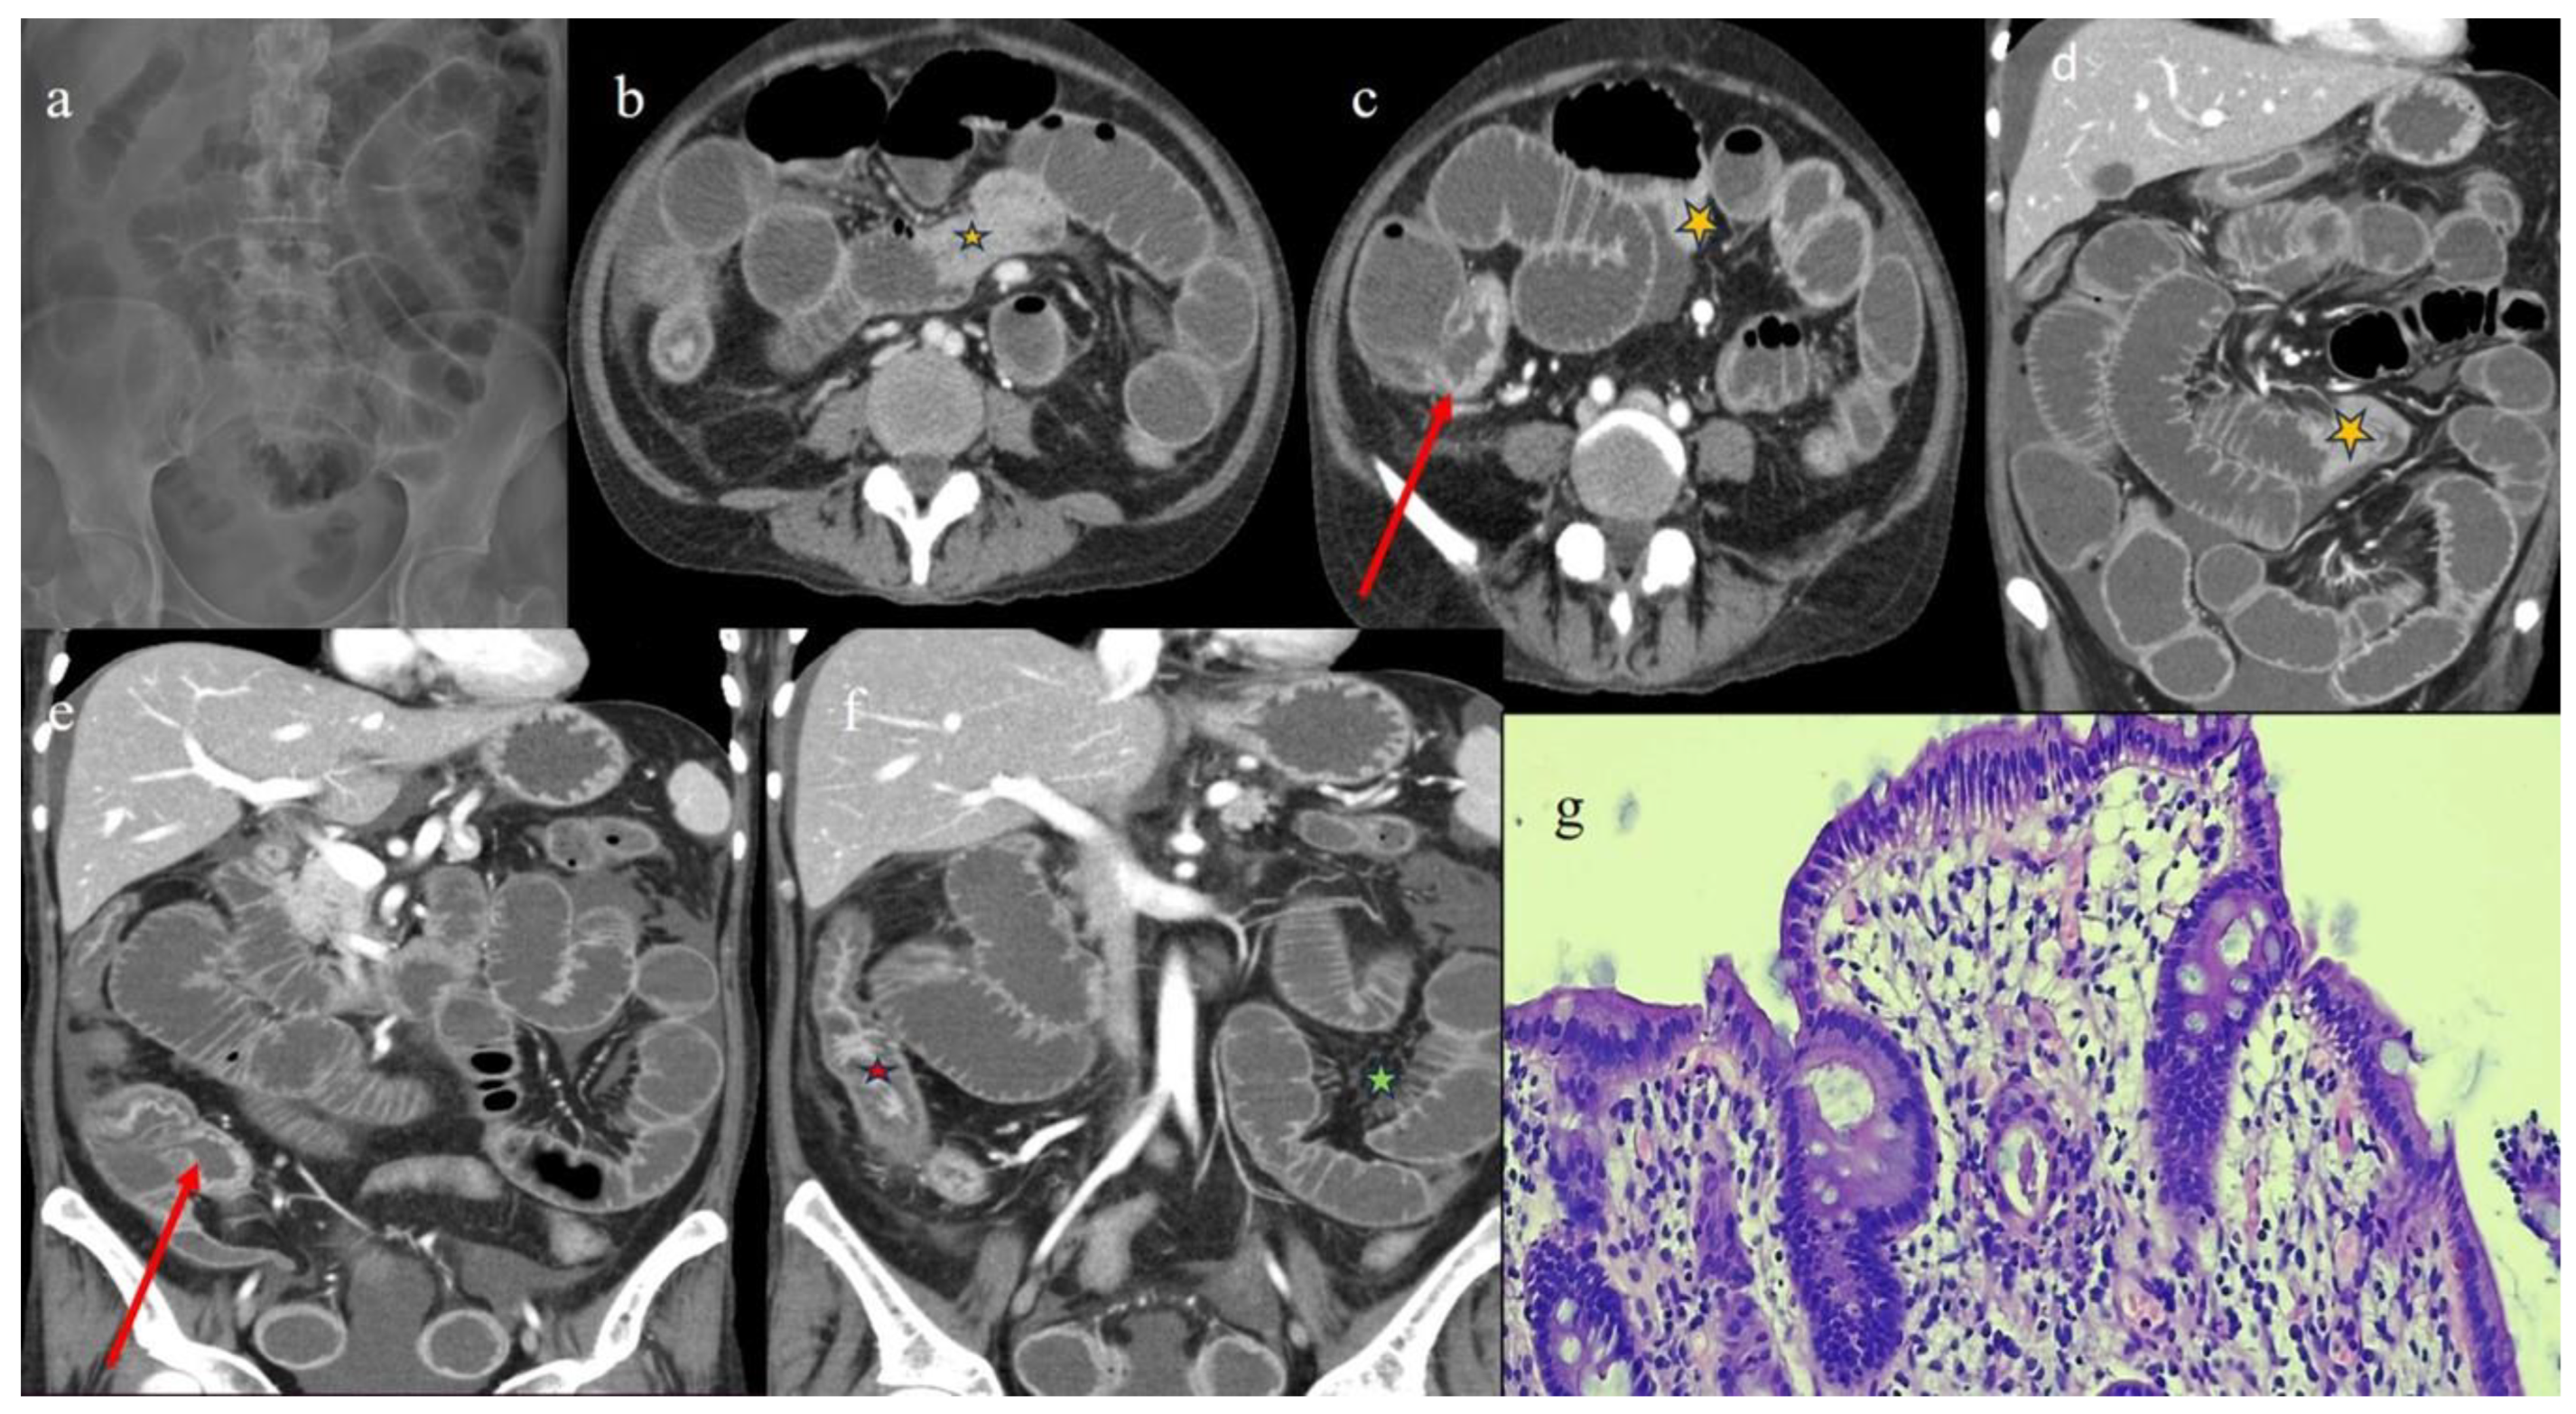

| 3 | P | P | Multisegmental thickness with stratified enhancement at the terminal ileus (on CECT control at 92 days). The CECT control at 129 days showed persistence of mild parietal thickness at terminal ileus and with mucosal enhancement | Diffuse parietal thickness with stratified enhancement (On CECT control at 92 days) The CECT control at 129 days showed colic fluid distension with mild diffuse mucosal enhancement | Diffuse comb sign, mild ascites, and poor reactive mesenteric lymph node | Hepatomegaly and mild gallbladder thickness |

| 4 | P | P | Intestinal diffuse homogeneous thickness with homogeneous mucosal enhancement (on CECT control at 66 days after the HSCT); diffuse small bowel involvement with increased parietal thickness on CECT control at 120 days | Appearance of multisegmental thickness on sigma and descending colon and stratified enhancement on transverse colon on the CT FU at 120 days | Diffuse comb sign and poor reactive mesenteric lymph node | Mild gallbladder thickness and persistence of biliary tract dilatation on follow-up CT |